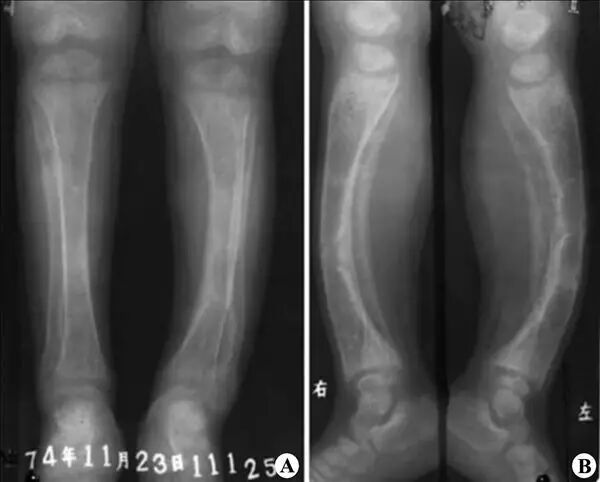

早在17世纪,人们就认识到佝偻病的区域性流行,在儿童中尤为多见。患佝偻病的儿童因全身钙磷代谢异常引起骨骼钙化不良,常出现骨骼畸形,严重影响生长发育。18世纪后期,人们已经发现鱼肝油能够治疗佝偻病,并推测可能是鱼肝油含有某种抗佝偻病的因子,但其中的机理一直不甚清楚。

佝偻病X射线图(图片来源:医学教育网)